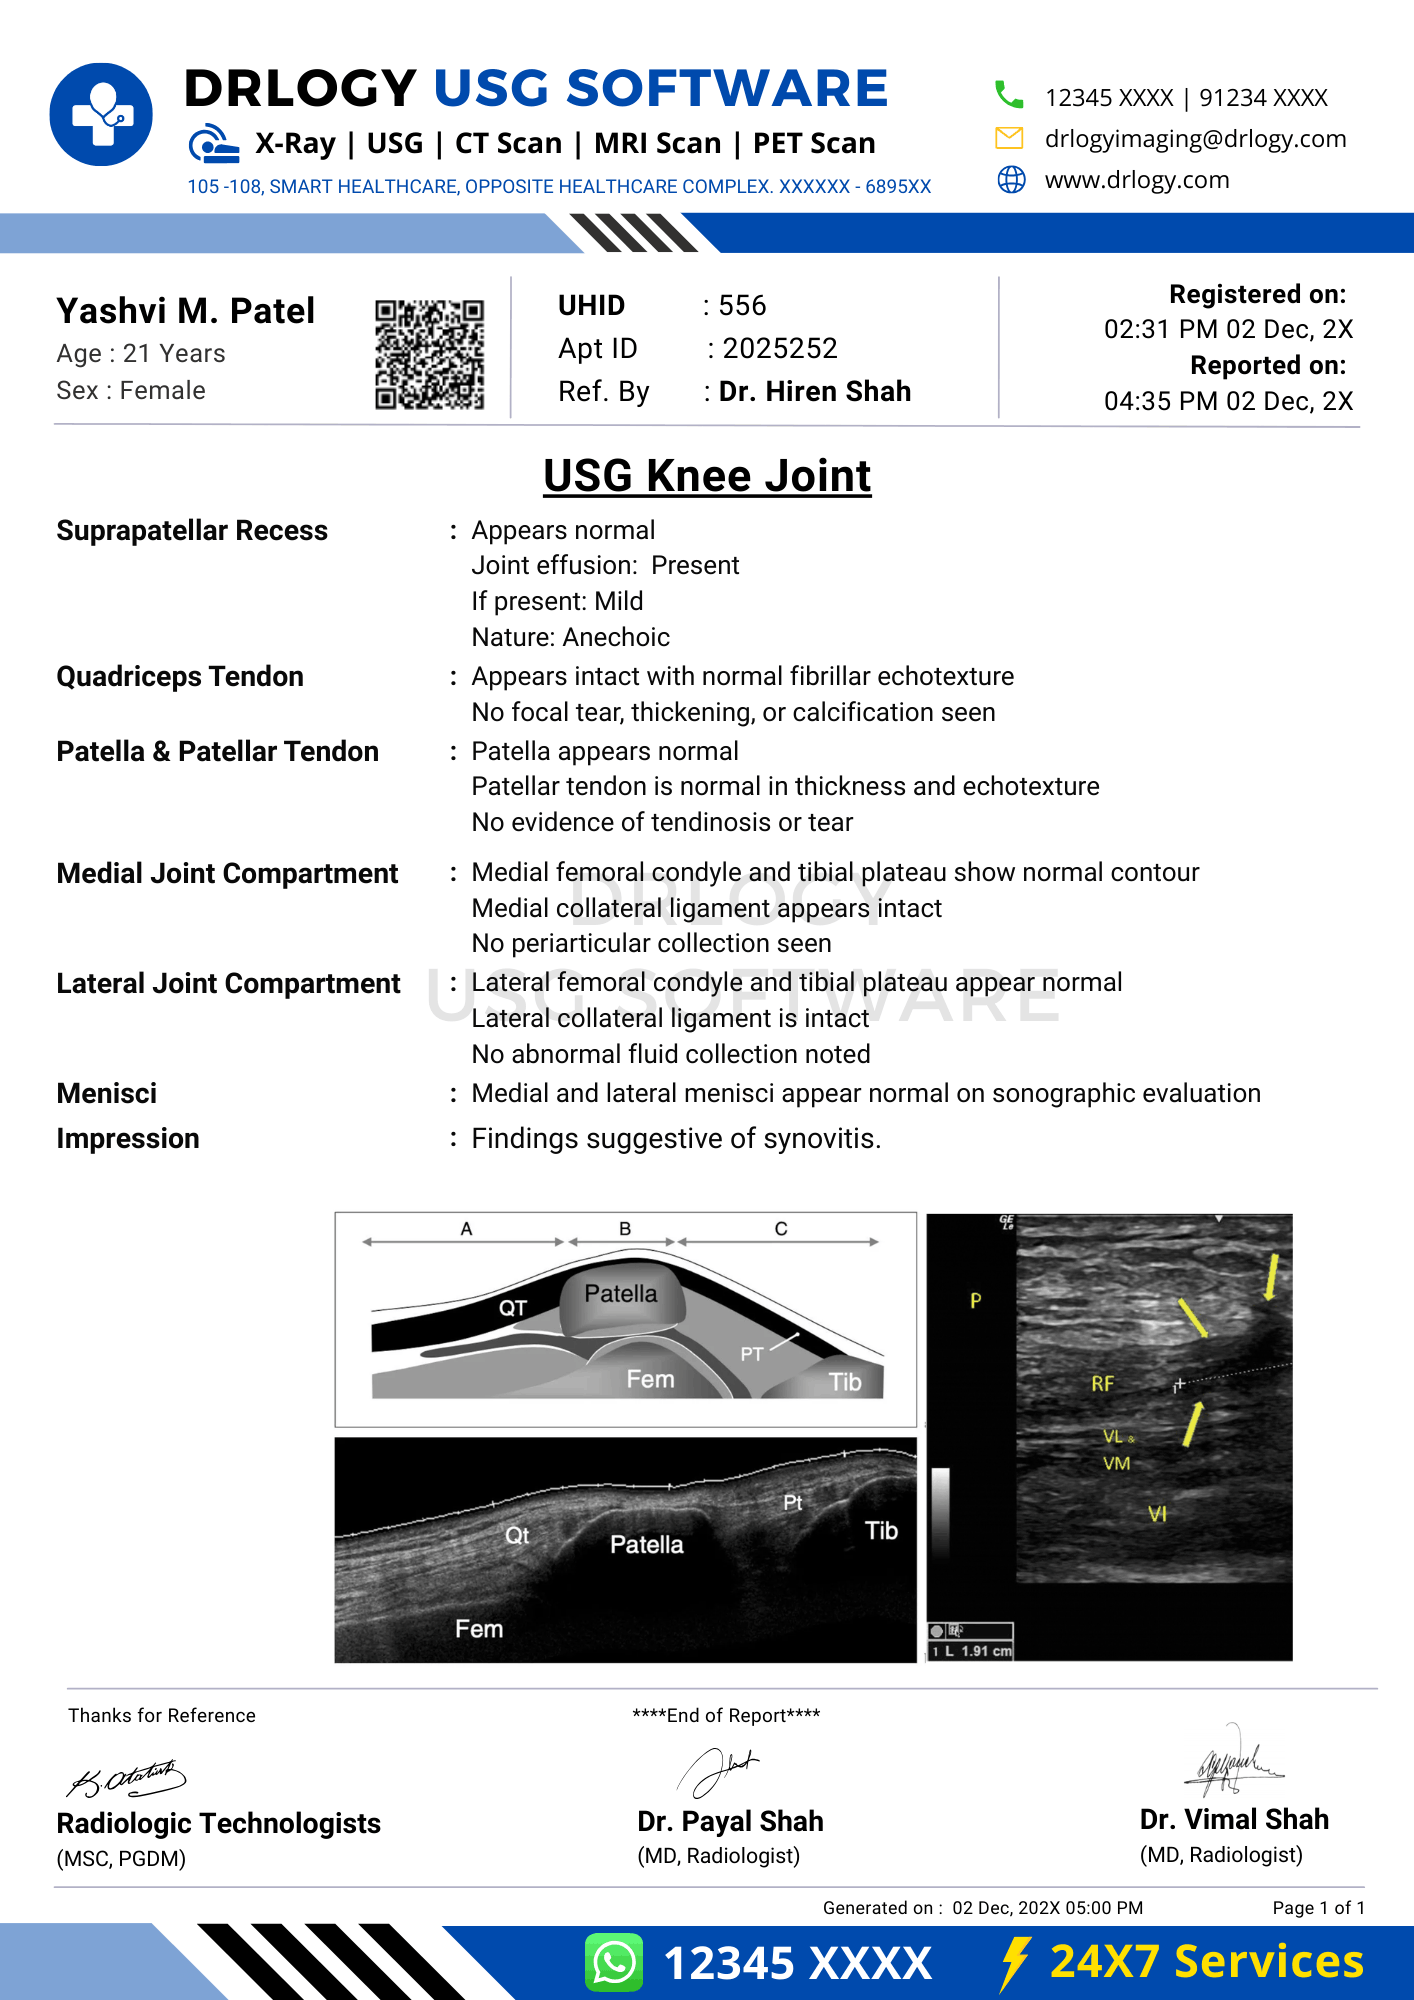

Normal USG Knee Joint Report Format (Sample)

- Patient & Study Information:

- Patient: [Name], [Age]

- Study Date: [DD-MM-YYYY]

Examination: USG Knee Joint

Clinical History / Indication:

Knee pain.

Technique / Protocol:

Ultrasound examination of the knee performed using high-frequency transducer.

Findings:

No joint effusion is seen. Quadriceps and patellar tendons appear intact. Collateral ligaments show normal echotexture. No focal soft tissue abnormality isentified.

Impression / Conclusion:

No significant sonographic abnormality detected in the knee joint.

Limitations:

No significant technical limitation noted.